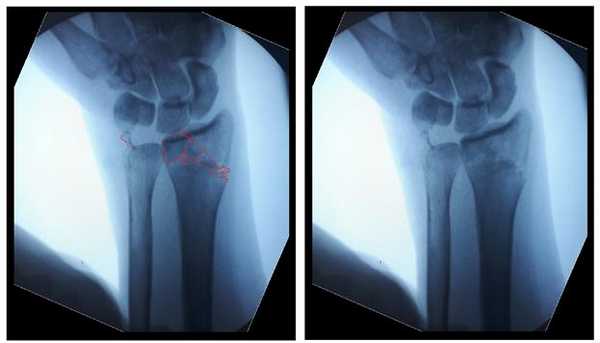

Пациентка М 65 лет, травма в результате падения на улице с опорой на кисть. В анамнезе множественные переломы, миеломная болезнь в стадии ремиссии (7 лет). После падения обратилась в РТП где ей была наложена гипсовая повязка. По какой то причине репозиция не производилась. После обращения в нашу клинику госпитализирована для оперативного лечения.

Внешний вид конечности после снятия гипсовой повязки. Рентгенограммы выполненные при помощи ЭОП на операционном столе выявили полное смещение всего дистального метафиза лучевой кости к тылу на целый поперечник.

Когда имеешь дело с таким переломом на фоне остеопороза становится ясно, что в метафизарной зоне будет «каша» из множества мелких отломков, и что суставная поверхность будет расколота минимум на 3 части.

В такой ситуации требуется надёжная фиксация при помощи пластины с угловой стабильностью, так как риск вторичного смещения в гипсовой повязке крайне высокий. При отказе от операции возможно лечение методом гипсовой иммобилизации, при этом перелом срастётся с небольшим смещением, но в функциональном плане рука будет работать удовлетворительно. По этой причине у пожилых пациентов с низкими функциональными запросами лечение может проводится методом гипсовой иммобилизации.

Но наша пациентка хотела максимального восстановления функции, силы хвата, амплитуды движений и нормальных анатомических взаимоотношений своей конечности, по этой причине было принято решение о выполнении операции.

Интраоперационно под контролем ЭОП произведена закрытая репозиция перелома.

После репозиции на рентгенограммах отчётливо виден многоооскольчатый, нестабильный характер перелома.